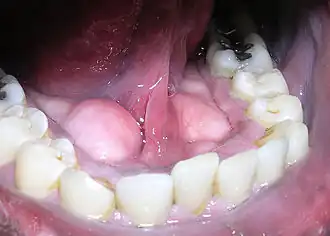

![]() Ejemplo de rodetes mandibulares. | ||

Un rodete mandibular (torus mandibularis) es un crecimiento anormal óseo en la mandíbula a lo largo de la superficie cercana a la lengua. Los rodetes mandibulares generalmente se presentan cerca de los premolares y sobre la ubicación de la unión del músculo milohioideo con la mandíbula.[1] En el 90% de los casos, se desarrollan rodetes en ambos lados (izquierdo y derecho), lo cual es una abrumadora situación de simetría bilateral.